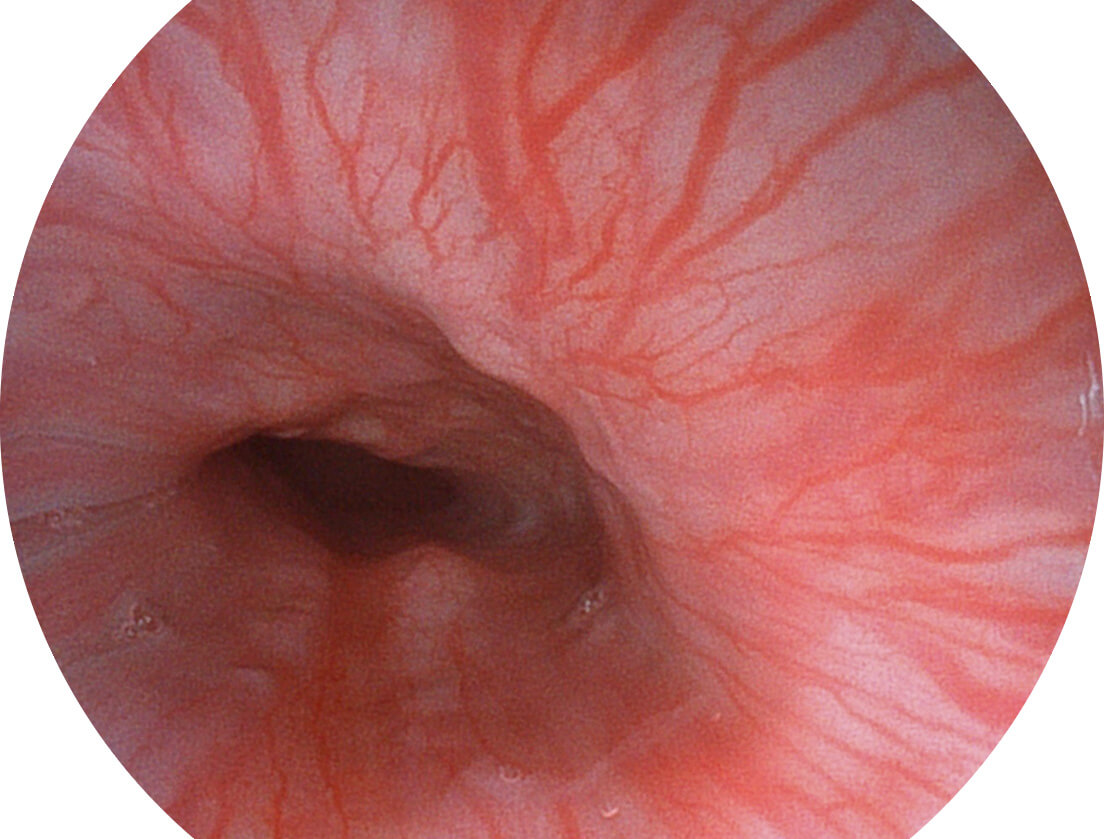

强调浅层黏膜结构的同时,保证照明亮度和提升浅层微血管与中层血管颜色对比度,病变边界更清晰。

白光图像

VIST图像